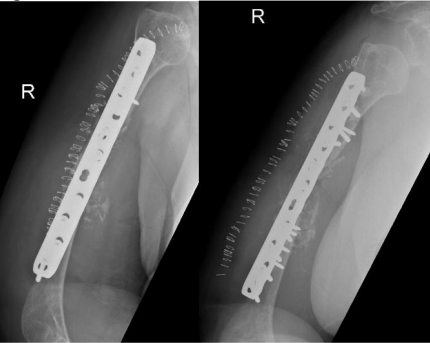

The patient was admitted and on 27 June 2018 underwent revision open reduction and internal fixation with the same surgical approach as the previous surgery. The fracture surfaces were trimmed until punctate bleeding was observed, and then the fracture was fixed with dynamic compression plating using a 10-hole 4.5 mm plate. An allograft was applied in the form of cancellous chips and putty bone substitute. Postoperative radiographs are shown in Figure 2.

Figure 2

On serial follow-ups, the patient was asymptomatic clinically and had no evidence of healing on radiographs. Then, on 15 May 2019, around 9 months post first revision she reported persistent localized pain to the fracture site, and with radiographic evidence of complete resorption of the allograft and non healed fracture a nonunion diagnosis was established (Figure 3).

Figure 03